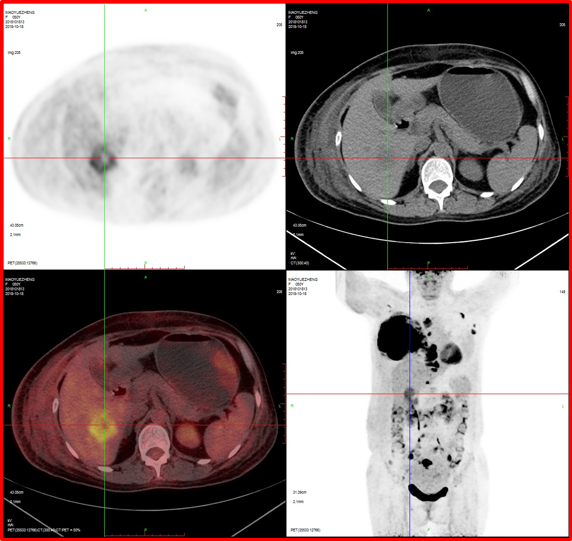

2、肝臟轉(zhuǎn)移。

4、肝脾多發(fā)轉(zhuǎn)移灶可能。